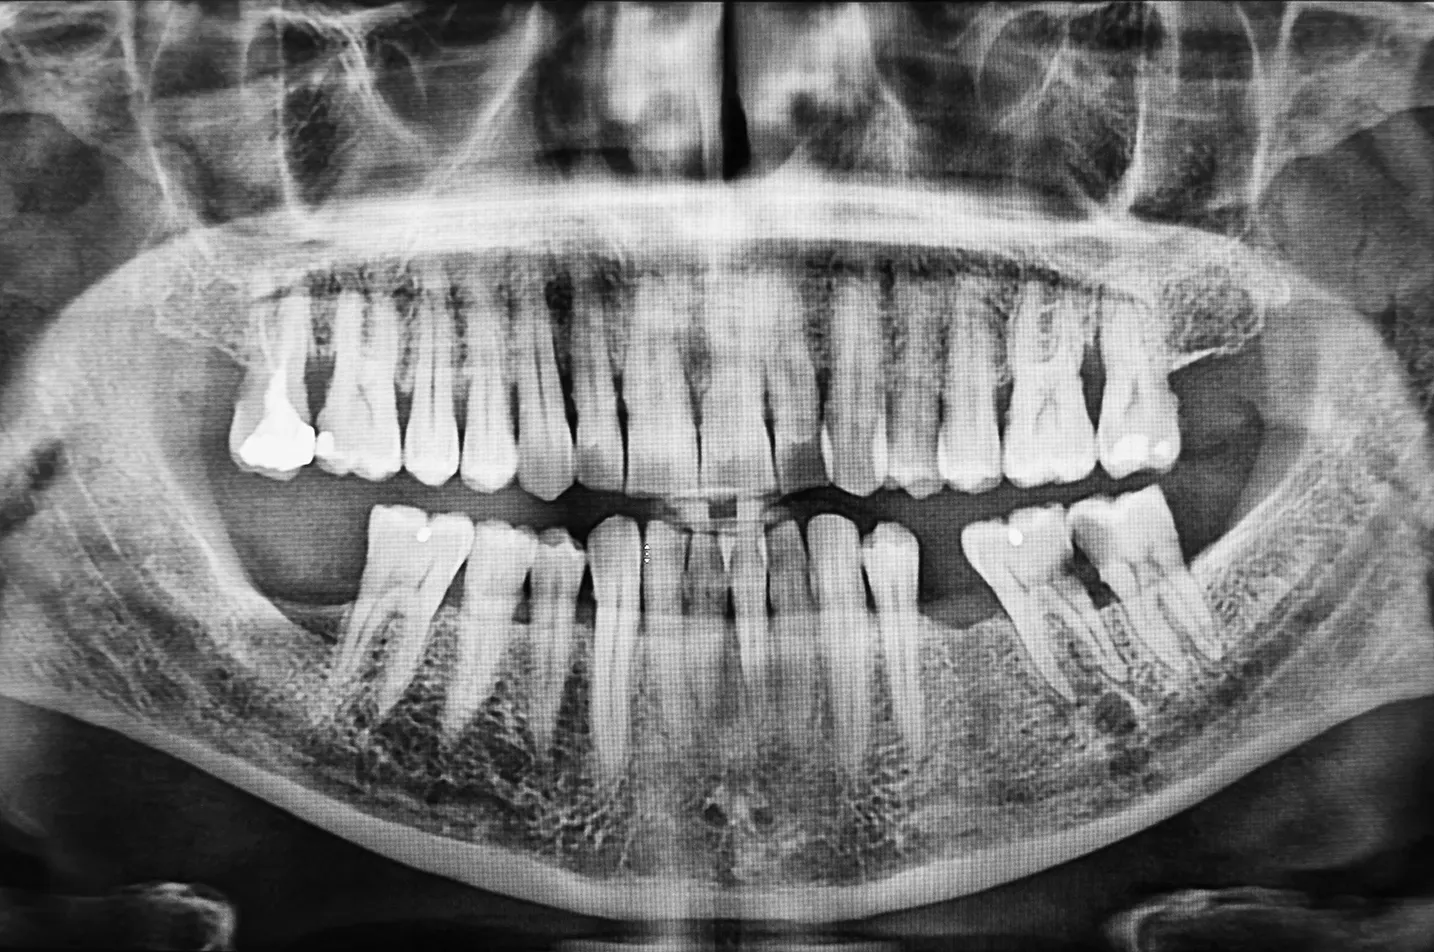

Dental x-rays or radiographs are very important. They allow the dentist to see things about your oral health that cannot be seen by the naked eye. These items include cysts (sacks of fluid that form on the roots of teeth), cancerous and non-cancerous tumors, hidden decay that occurs between teeth, tartar buildup below the gum line, quality and fit of dental restorations that extend between the teeth, and the location of teeth that haven’t grown all the way in.

By using an x-ray to diagnose these problems, we can help save you money in the long run from surgeries or other treatments that might become necessary if we didn’t find the problem. In some cases, where dental x-rays show the location of tumorous growths, x-rays can be responsible for saving your life.